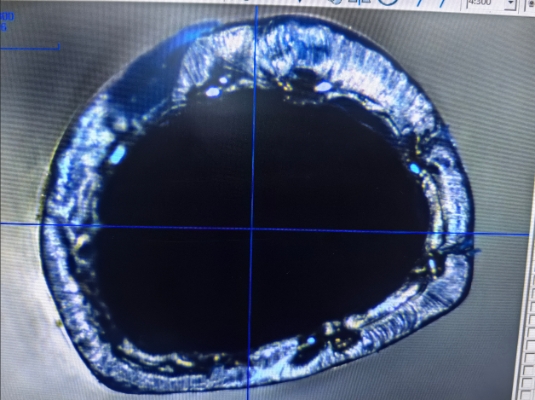

Un cateter împletit profilat este un cateter medical proiectat cu o structură împletită și o formă de secțiune transversală profilată specific. Este utilizat de obicei în proceduri medicale care necesită debite mari și stabilitate. Caracteristica notabilă a acestui cateter este combinația dintre pereții săi interiori și exteriori cu materiale împletite, care îmbunătățește transmiterea fluidelor, menținând în același timp flexibilitatea și durabilitatea.

Aspectul „profilat” al acestui cateter se referă la faptul că secțiunea sa transversală nu este un simplu cerc, ci mai degrabă o formă special concepută, cum ar fi o elipsă, poligon sau alte forme necirculare. Stratul împletit adaugă rezistență, permițând cateterului împletit profilat să reziste atât la presiunile interne, cât și la cele externe, menținându-și forma și funcționarea chiar și în condiții de stres.